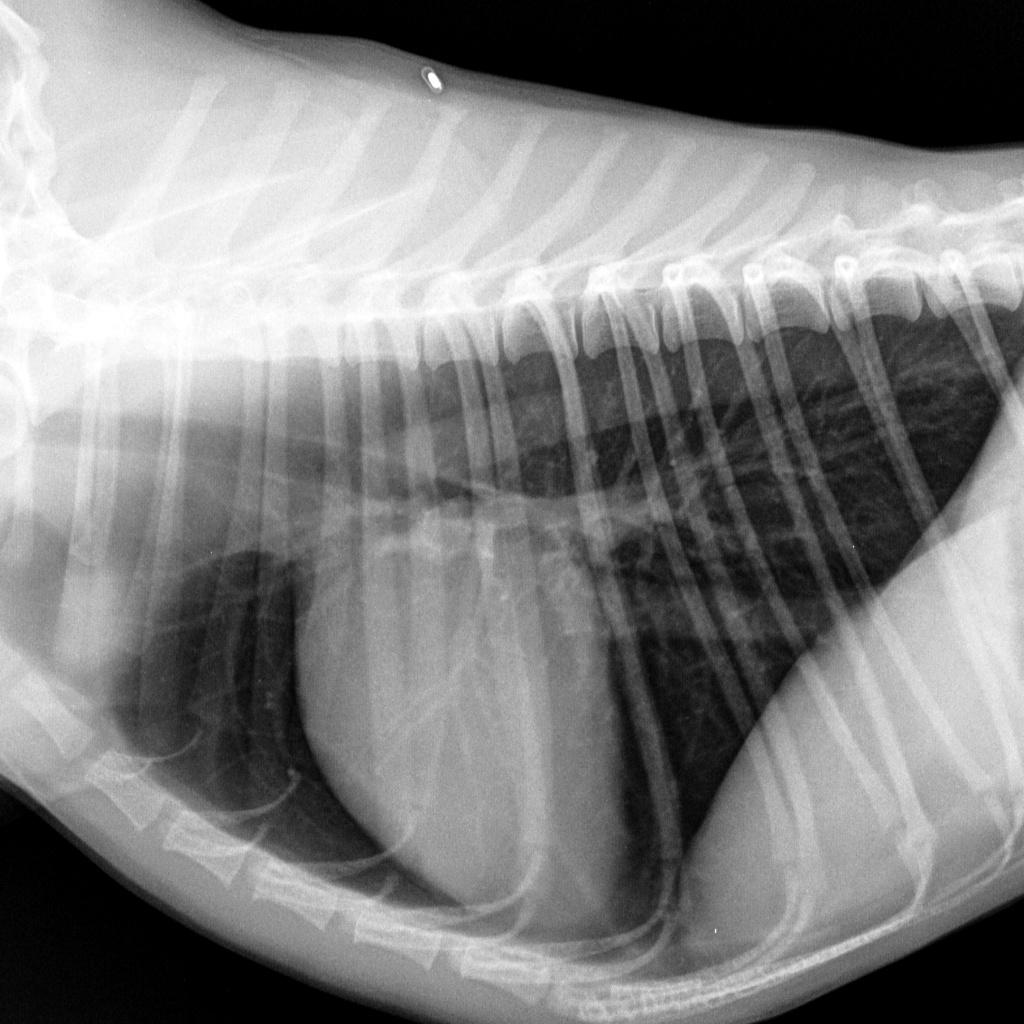

Отделение рентгенодиагностики оборудовано современной системой получения рентгеновских снимков и позволяет получать изображения грудной клетки в высоком разрешении (сердце, сосуды, легкие, трахея и др.). Это позволяет заметить даже незначительные изменения размеров сердца, новообразования маленьких размеров, верно оценить структуру тканей.

Сердце и сосуды грудной полости собаки в норме (лево-правая боковая проекция лежа)